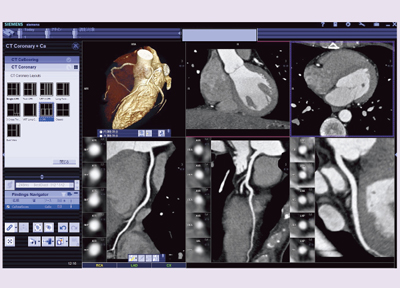

心臓CT検査は,循環器内科,心臓血管外科,小児科から電子カルテを通してオーダを受け,RISを介してDefinition Flashと,画像解析処理システム「syngo.via」にワークリストが送られる。syngo.viaでは,前処理と解析処理がほぼ自動で行われ,医師がsyngo.viaにレポートを記載し送信している(図1)。当センターはsyngo.viaの端末を十数台設置し,外来や病棟,アンギオ室,オペ室などから閲覧でき,随時医師が解析することもできる(図2)。

![]() 図1 心臓病センターでの心臓CTのワークフロー |

![]() 図2 syngo.viaによる画像閲覧 |